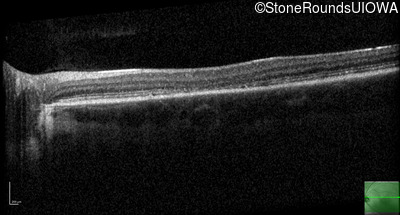

Age at visit: 15 years

Age at visit: 16 years